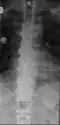

Confluent ossification of multiple contiguous vertebral bodies in diffuse idiopathic skeletal hyperostosis (DISH)

"Melted candle wax" appearance of calcification and ossification in diffuse idiopathic skeletal hyperostosis (DISH). Note the preponderance on the patient's left side (right side of image).